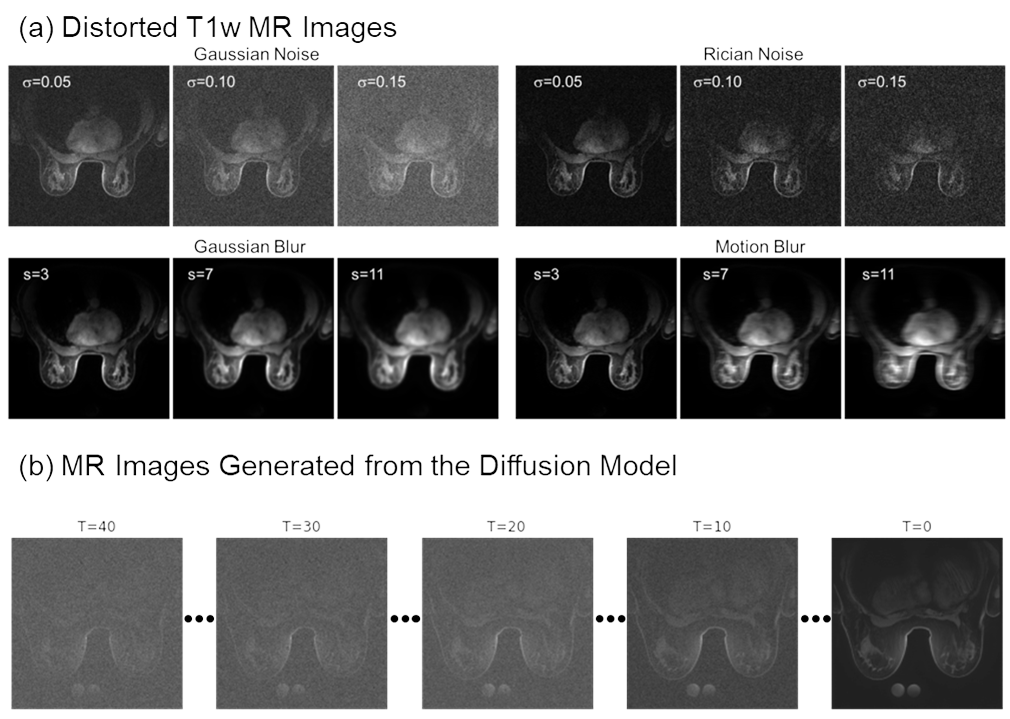

Noise and blurriness are two main types of image losses that exist in MRI, especially non-proton MR images. [28] As shown in Fig. 2(a), two noise types, Gaussian noise and Rician noise, and two blurriness types, Gaussian blur and Motion blur, are simulated in this paper. The two types of noise, Gaussian and Rician noise, are simulated with a random standard deviation () from 0 to 0.25 of the maximum image intensity and added to the high-quality proton T1-weighted (T1w) MR images. Regarding blurriness, a Gaussian blur and a horizontal motion blur filter with a random size (s) from 3 to 51 pixels is applied to the T1w MR images using OpenCV [29]. Even though there is not a strictly definable metric for absolute image quality score for many types of image distortions, increases in the noise standard deviation and blur filter kernel size are assumed to be directly associated with worse image quality. Noise and distortion simulations are then used to measure the alignment of IQA metrics’ predictions for their ability to evaluate image quality.

While directly adding Gaussian or Rician noise is straightforward, it means that the pattern of noise is purely random and does not consider image content or contextual information. To generate a more complex noise model which is less uniform, this paper also generates noisy images using a diffusion model, Denoising Diffusion Probabilistic Models (DDPM) [30].

In a DDPM, the noise added at each timestep is typically conditional on the current state of the image. This means that the noise can adapt based on the evolving features of the image through the diffusion process. This could result in noise patterns that are less predictable and possibly more akin to real-world noise, such as may occur with imperfections in magnetic field gradients. Fig. 2(b) gives an example of the synthetic noisy MR images generated from DDPM. means the timestep at which the denoising process stops before reaching a clean image. Lager correspond to larger noise levels and worsening image quality. The IQA metrics’ evaluation performance can be assessed based on the correlation between the evaluation results and the timesteps.